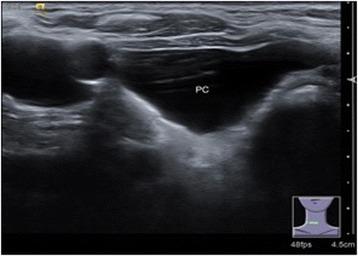

There were 22 female and 10 male participants with a median age of 46.7 years old (27-76 years old). Only two cysts were found in the superior mediastinum. The rest were located under the lower pole of the thyroid. All of the patients underwent ultrasonography scans and serum parathyroid hormone (PTH) assays. Three patients had elevated serum PTH levels, and they were further scanned with Tc99m sestamibi as functional cysts. In 29 cases of nonfunctional cysts, 3 cases were preoperatively diagnosed by cystic aspiration with PTH detection. The rest were diagnosed by postoperative immunopathology. All of the patients underwent cystectomy, and 24 patients also underwent thyroidectomy. There was a significant difference in cyst diameter size between the cystectomy alone and cystectomy with thyroidectomy groups (4.0 ± 2.0 vs 1.5 ± 1.0 cm; p < 0.05). No participant experienced recurrence during the median 36 months of follow-up.

Cystic lesions located under the lower pole of the thyroid gland should be considered to have originated at the parathyroid gland. Cystic aspiration with PTH detection or postoperative immunopathology can lead to a definitive diagnosis. Cystectomy is still a commonly used and effective treatment.

共有22例女性和10例男性参与者,中位年龄为46.7岁(27 - 76岁)。仅2个囊肿位于上纵隔,其余均位于甲状腺下极。所有患者均接受了超声扫描和血清甲状旁腺激素(PTH)检测。3例患者血清PTH水平升高,作为功能性囊肿进一步行99m锝甲氧基异丁基异腈扫描。29例非功能性囊肿中,3例术前通过囊肿穿刺并检测PTH确诊,其余通过术后免疫病理学确诊。所有患者均接受了囊肿切除术,24例患者还接受了甲状腺切除术。单纯囊肿切除术组与囊肿切除联合甲状腺切除术组的囊肿直径大小存在显著差异(4.0±2.0 vs 1.5±1.0 cm;p<0.05)。在中位36个月的随访期间,无参与者复发。

位于甲状腺下极的囊性病变应考虑起源于甲状旁腺。囊肿穿刺检测PTH或术后免疫病理学检查可明确诊断。囊肿切除术仍是常用且有效的治疗方法。